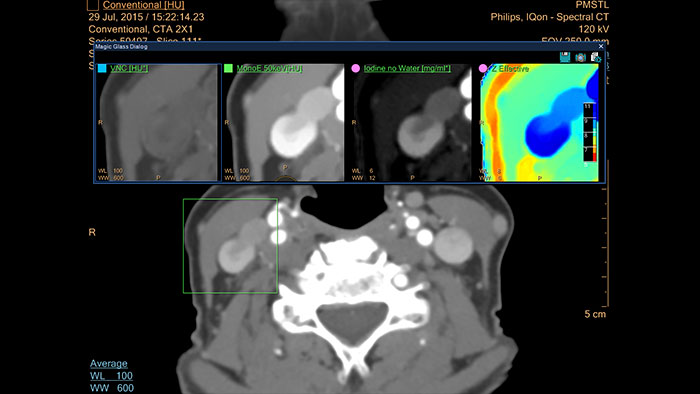

- Spectral Viewer

CT Spectral Viewer

IQon Spectral CT* Functionality

The spectral viewer is optimized for analysis of spectral data sets from the IQon Spectral CT Scanner. Obtain a comprehensive overview of each patient quickly and easily, quantify quickly, and assist in diagnosis. It is designed to accommodate general spectral viewing needs with additional tools to assist in CT images analysis.

Benefits

- Enhances the conventional image by overlaying an iodine map.

- Visualization of virtual non-contrast images.

- Images at different energy levels (40-200 keV).

- Switching to various spectral results can be done through a viewport control.

- Manage presets to create user/site-specific presets.

- Lesion characterization using scatter plots.

- Tissue characterization using attenuation curves.